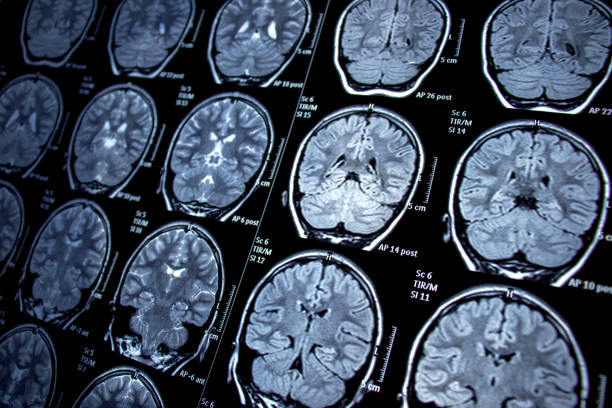

圖1:癲癇的主要潛在病理生理學(xué):神經(jīng)層面的異常興奮和抑制信號(hào)。

干細(xì)胞可以改善信號(hào)通路的這種不平衡,同時(shí)促進(jìn)癲癇發(fā)作后大腦的修復(fù)。